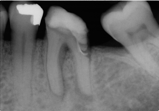

Surgical Endodontic Treatment

Hemisection with Cast Post and Core